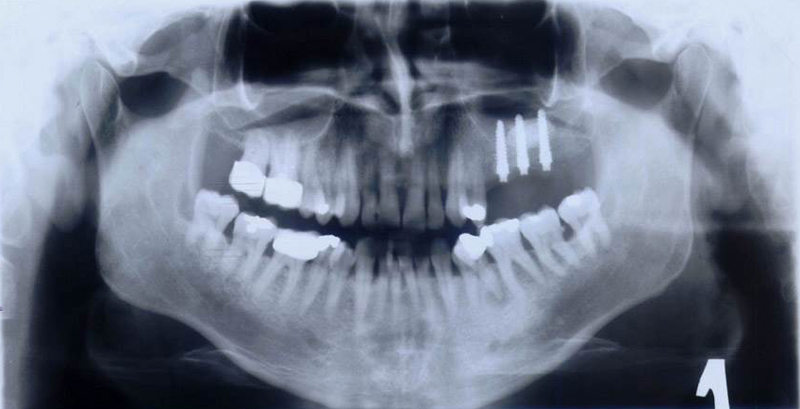

Při ztrátě molárů a premolárů v horní čelisti a jejich náhradě implantáty se často setkáváme s nedostatečnou vertikální nabídkou kosti pod čelistní dutinou, často doprovázenou i nedostatečnou horizontální nabídkou a sníženou kvalitou kosti

(v oblasti 2. premoláru v 50%, v oblasti moláru až v 80% případů nedostatečná kostní nabídka)

Od roku 1985 je tento problém řešen augmentační operací nazývanou sinus lift.

Jedná se o vyzvednutí membrány, která čelistní dutinu vystýlá, pod vyzvednutou membránou vznikne kapsa, kam se umístí augmentační materiál, do kterého se zavedou implantáty.

Vhojení implantátů se při této operaci prodlužuje na 6-12 měsíců.